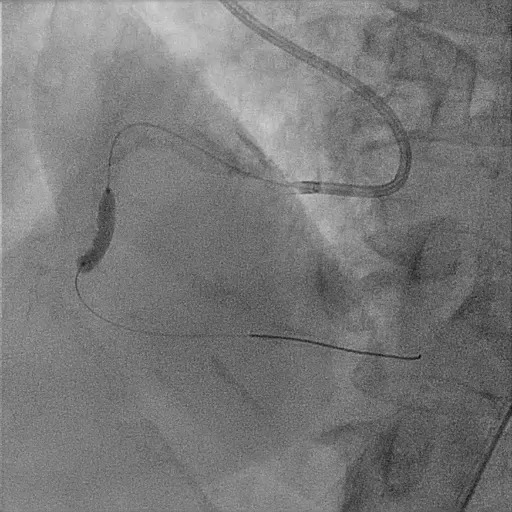

Radial approach. AL guided 6.5 3.5F. Runthrough wire down to distal RCA. predilate 2.5x15mm wire cannot pass stenotic lesion.

Change tp 1.5x15mm ballon to rate burst. Unable to cross IVUS catheter in. Predilate 2.5x15mm wire high pressure. Proceed with Lithix ballon 3.5x14mm preparation from distal to proximal RCA , multiple time ( distal 8atm x 3 , proximal 10-12 atm multiple slow inflation. Post Lithix , angiogram show good TIMI3 flow, mild linear dissection noted , good preparation. We proceed with 1xDCB over distal RCA and 1x DCB over midRCA 4.0X30 at 9atm. Post DCB noted recoil over distal RCA , then proceed with 1XDES 4.0x34 at 12atm at distal RCA. prox RCA treated with 1x DES till ostial RCA 4.0X34mm at 12atm. IVUS run post PCI , good stent expansion and opposition. Angiogram Post stent good TIMI 3 flow , no recoiled , accepted linear dissection . Patient well post PCI discharge well the next day.